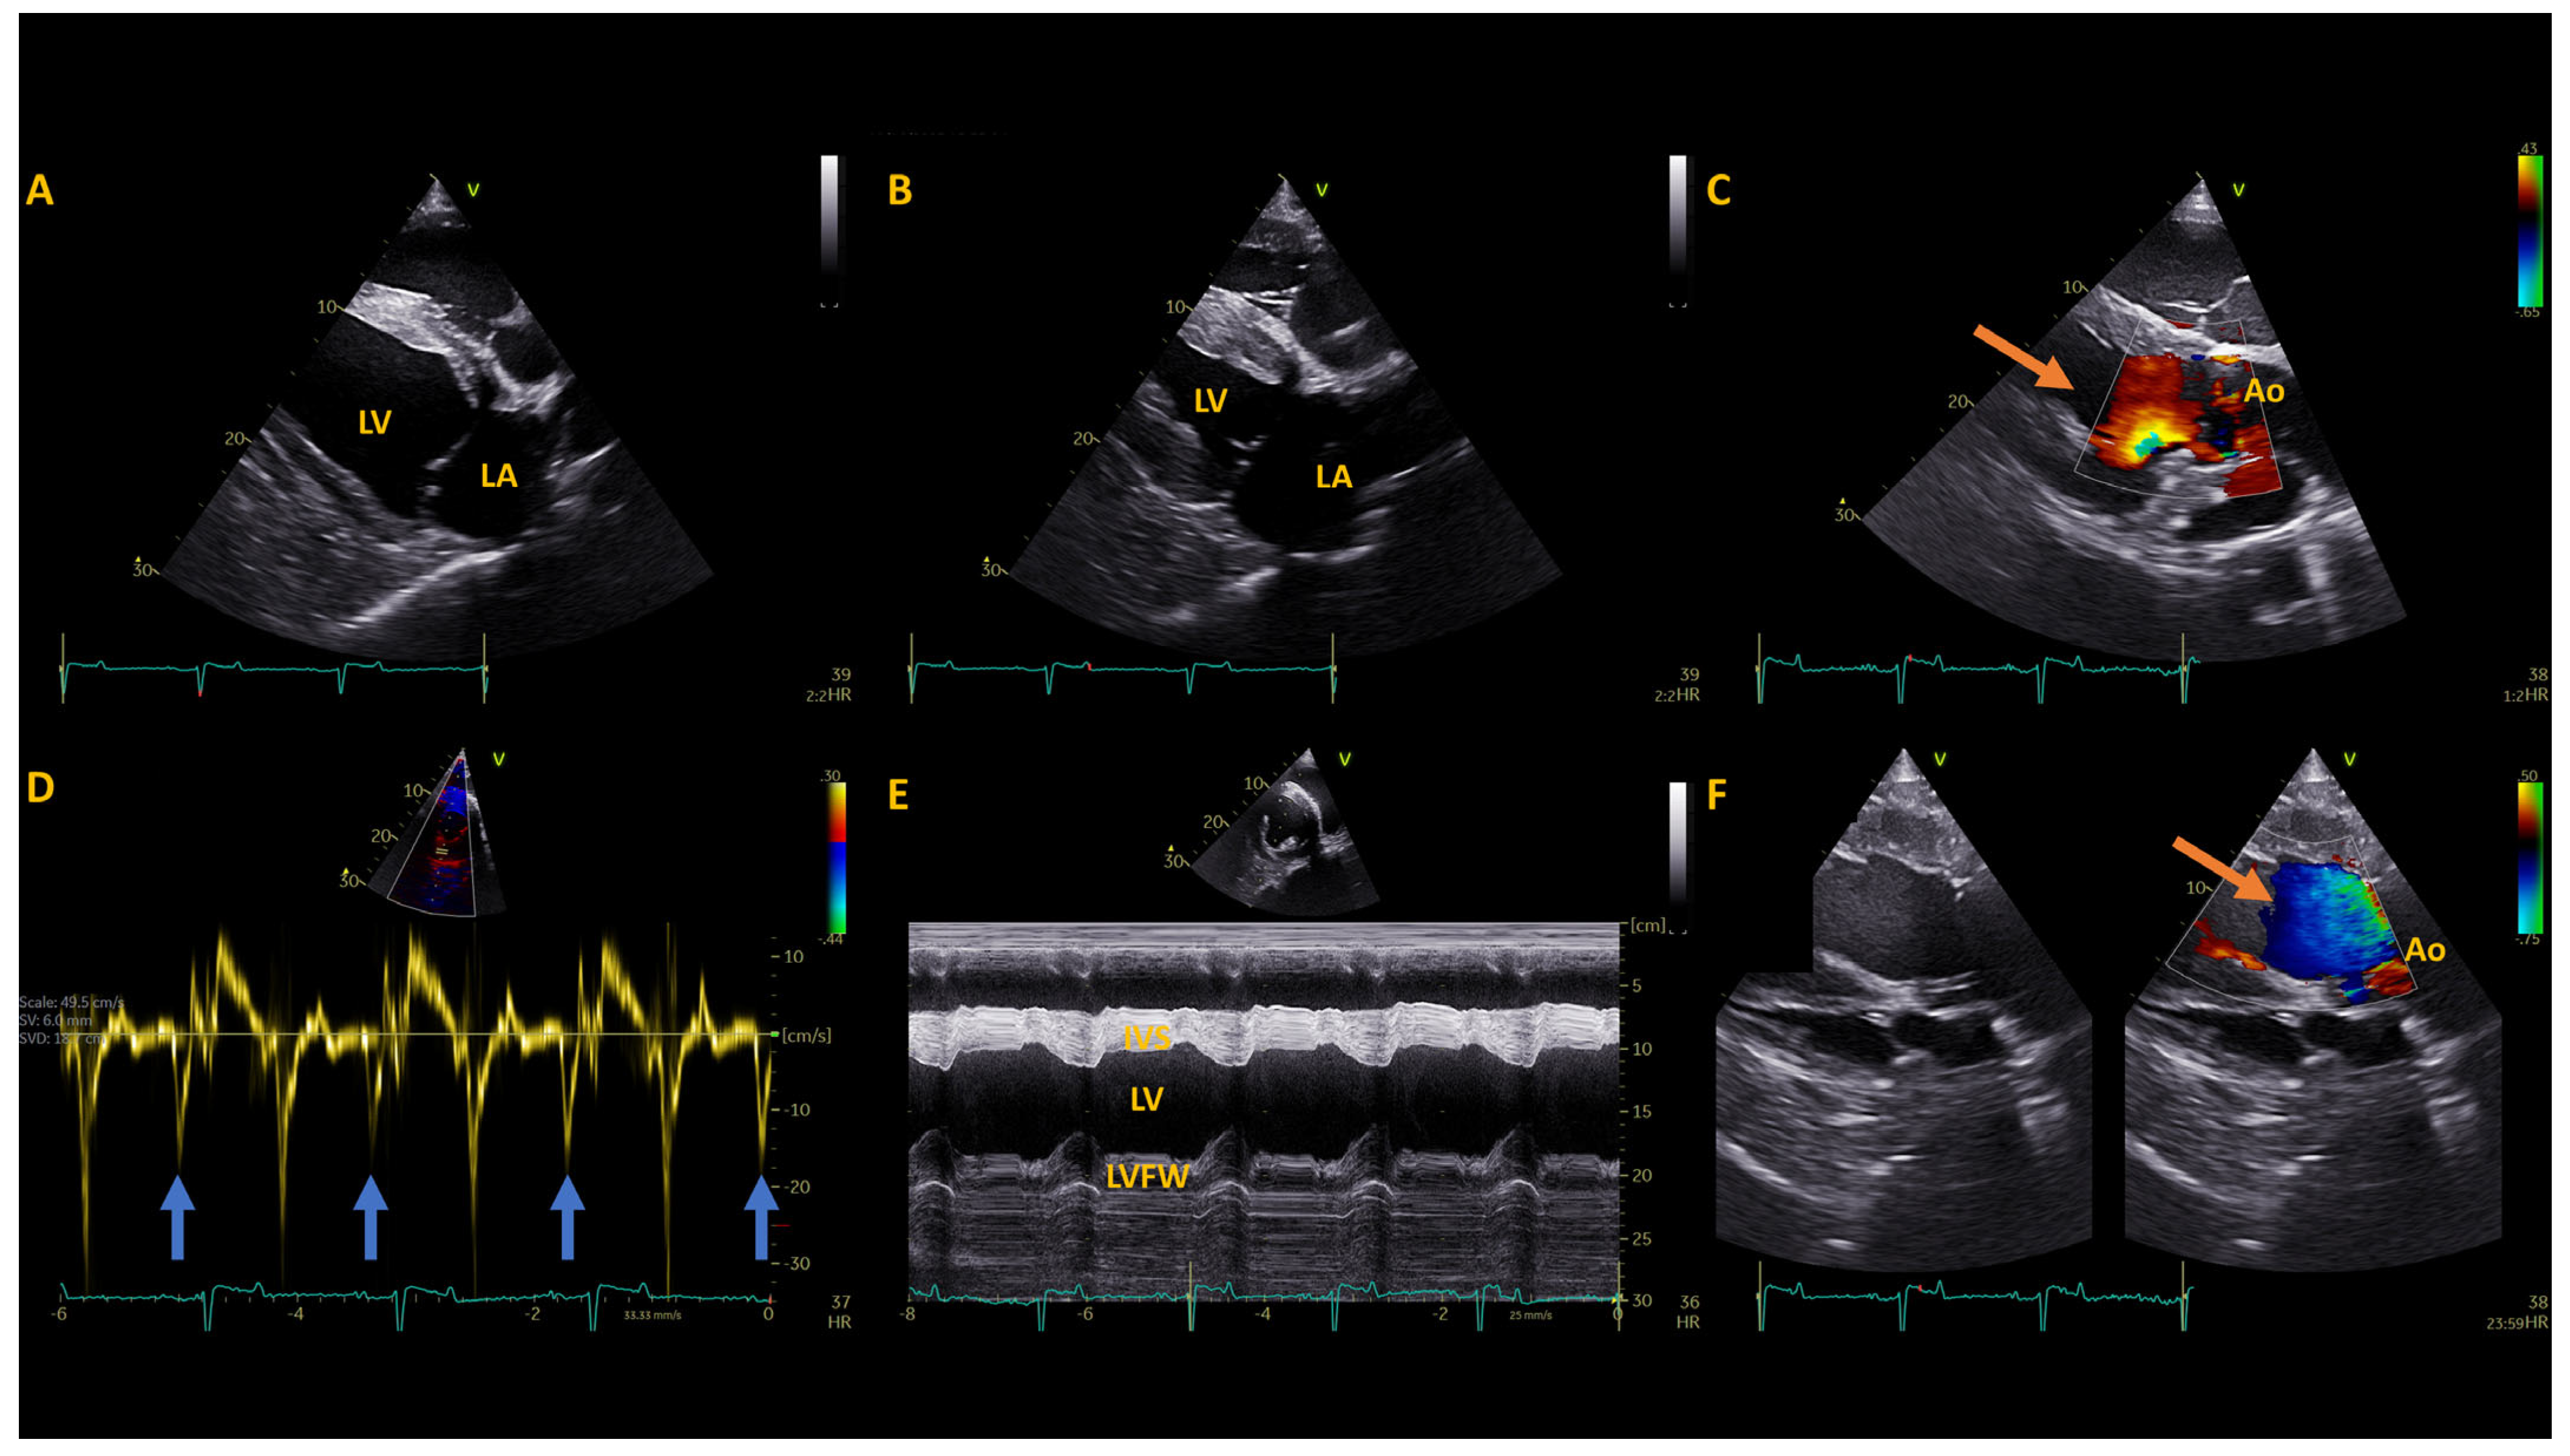

3.1. Post-Operative Diagnostics

| Measurement (Units) | Available References (mean ± SD) | Pre-Operative | 1 Year Post-Operative | 2 Years Post-Operative |

|---|---|---|---|---|

| Left Atrium | ||||

| LAAmax (cm2) | 92.8 ± 5.0 | 71.4 | 71.8 | 70.9 |

| LADmax (R) (cm) | 11.9 ± 0.7 | 10 | 10.4 | 9.8 |

| LA FAC active (%) | 20 ± 7.0 | 41 | 34 | 30 |

| LADmax (L) (cm) | 12.9 ± 0.5 | 13.3 | 13.1 | 11.2 |

| LAAmax sx (cm2) | 108.8 ± 12.2 | 102.9 | 87.4 | 74.6 |

| LA/Ao (Sx) Ratio | 2.5 ± 0.3 | 2.7 | 2.2 | 2.1 |

| Left Ventricle | ||||

| IVSd (cm) | 2.8 ± 0.3 * | 3.2 | 3.3 | 2.7 |

| LVIDd (cm) | 11.1 ± 1.5 * | 9 | 8.9 | 9.0 |

| LVFWd (cm) | 3.3 ± 0.3 * | 2.6 | 2.6 | 2.8 |

| IVSs (cm) | 4.4 ± 0.4 | 5 | 4.7 | 4.4 |

| LVIDs (cm) | 6.7 ± 1.3 * | 4.2 | 4.6 | 5.0 |

| LVFWs (cm) | 4.4 ± 0.4 | 4.3 | 3.9 | 3.9 |

| FS (%) | 40.4 ± 5.7 * | 54 | 49 | 44 |

| LVIVd (ml) | 1475 ± 200.7 | 694 | 672 | 757 |

| LVIVs (ml) | 412 ± 81.6 | 146 | 148 | 189 |

| SV (mL) | 1065 ± 139.2 | 548 | 524 | 568 |

| CO (L) | 37.1 ± 6.02 | 30.6 | 30.4 | 21.2 |

| EF (%) | 71 ± 4.9 | 79 | 78 | 75 |

| MWT (cm) | 3.05 ± 0.2 * | 2.9 | 2.9 | 2.8 |

| RWT | 0.52 ± 0.2 * | 0.65 | 0.66 | 0.61 |

| LAD/LVID ratio | 1.1 ± 0.1 | 1.11 | 1.17 | 1.09 |

| HR (bpm) | 38 ± 4.4 * | 50 | 57 | 37 |

| Great Vessels | ||||

| PADed (cm) | 6.5 ± 0.47 | 5.8 | 5.8 | 5.9 |

| AoDed (cm) | 7.0 ± 0.9 * | 6.6 | 6.7 | 6.5 |

| PAed-sx (cm) | 5.0 ± 0.31 | 4.1 | 4.1 | 4.7 |

| AoAsx (cm2) | 45 ± 5.5 | 38 | 39.5 | 36 |

| Ao/PA (sx) Ratio | 1.4 ± 0.1 | 1.6 | 1.6 | 1.4 |

| Tissue Doppler Imaging | ||||

| IMP | 0.38 | 0.29 | 0.44 | |

| Em/Am | 3.1 ± 0.8 | 1.7 | 1.2 | 1.9 |

| Velocity | ||||

| AoVmax (m/s) | 1.1 | 1.2 | 0.9 |